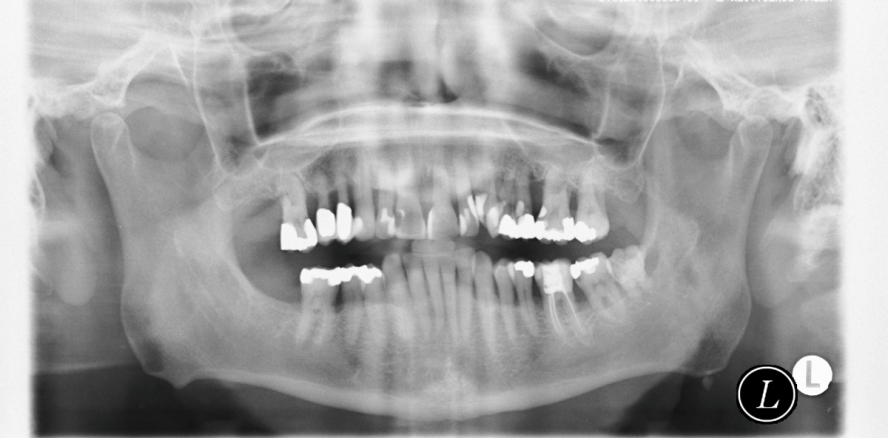

befinden. In diesem Falle muss eine vollständige parodontale Diagnostik erfolgen (Eickholz, 2007a). Zusätzliches diagnostisches Hilfsmittel können Röntgenbilder sein. Selbst Bissflügelaufnahmen, die im Zuge einer Kariesdiagnostik bei jungen Patienten von Zeit zu Zeit angefertigt werden, können eine beginnende AgP bereits frühzeitig aufdecken (Cogen et al., 1992; Sjodin et al., 1993). Gerade für eine solch lokalisierte Erkrankungsform, bei welcher häufig die Inzisiven und ersten Molaren zuerst betroffen sind (Lang et al., 1999), sollte grundsätzlich eine Beurteilung des Verlaufs des Limbus alveolaris erfolgen. Neben einer familiären Häufung der Parodontalerkrankung und ein außer der Parodontitis klinisch gesunder Patient gilt insbesondere das rasche Voranschreiten der parodontalen Destruktion als primäres Kennzeichen der AgP (Armitage, 1999; Lang et al., 1999). Diese drei Hauptmerkmale wirken insgesamt leicht beurteilbar, jedoch kann beispielsweise bereits die

Unabhängig von der Diagnose „chronische“ oder „aggressive Parodontitis“ – gute Erfolgsaussichten bestehen bei konsequenter Therapie und Nachsorge für beide Erkrankungsformen. Durch eine lebenslange und individuell angepasste Kontrolle des dentalen Biofilms ist es möglich, den parodontalen Zustand zu stabilisieren bzw. zumindest die Progression der Erkrankung deutlich zu verzögern (Abb. 1 und 2). Somit ist in den meisten Fällen ein Zahnverlust nach Parodontitistherapie unter der Voraussetzung einer regelmäßigen UPT ein eher seltenes Ereignis mit rund 0,1 Zahn/Jahr über einen Untersuchungszeitraum von zehn Jahren (Chambrone et al., 2010; Nibali et al., 2013). Selbst bei Patienten mit fortgeschrittener AgP oder CP werden Überlebensraten der Zähne von 60 bis 97 Prozent innerhalb von einem Jahrzehnt beschrieben (Kamma und Baehni, 2003; Pretzl et al., 2008; Mros und Berglundh, 2010; Bäumer et al., 2016; Graetz et al., 2016). Für jegliche parodontale Behandlungsstrategie gilt jedoch: Je jünger die Patienten und je lokalisierter die Destruktion initial ist, insbesondere bei AgP, umso höher sind die Erfolgsaussichten (Merchant et al., 2014).